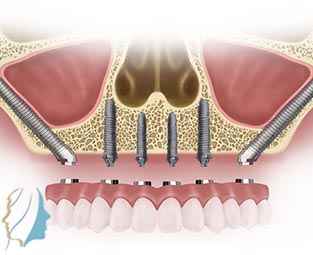

ΖΥΓΩΜΑΤΙΚΑ - ΠΕΡΥΓΟΕΙΔΗ - ΔΙΑΡΙΝΙΚΑ ΕΜΦΥΤΕΥΜΑΤΑ

Ζυγωματικά, πτερυγοειδή, διαρινικά εμφυτεύματα

Αντιμετωπίζουμε την ατροφική άνω και κάτω γνάθο με άμεση τοποθέτηση δοντιών χωρίς χρήση οστικών μοσχευμάτων. Τα ζυγωματικά, τα πτερυγοειδή και τα διαρινικά εμφυτεύματα χρησιμοποιούνται εκεί όπου η έλλειψη οστού καθιστά αδύνατη την αποκατάσταση με τα συμβατικά εμφυτεύματα.

Η οστεοενσωμάτωσή τους είναι απόλυτα προβλέψιμη και στις περισσότερες των περιπτώσεων επιτρέπει την άμεση αποκατάσταση με δόντια αποφεύγοντας την πολύμηνη αναμονή μετά τη τοποθέτηση συμβατικών εμφυτευμάτων.